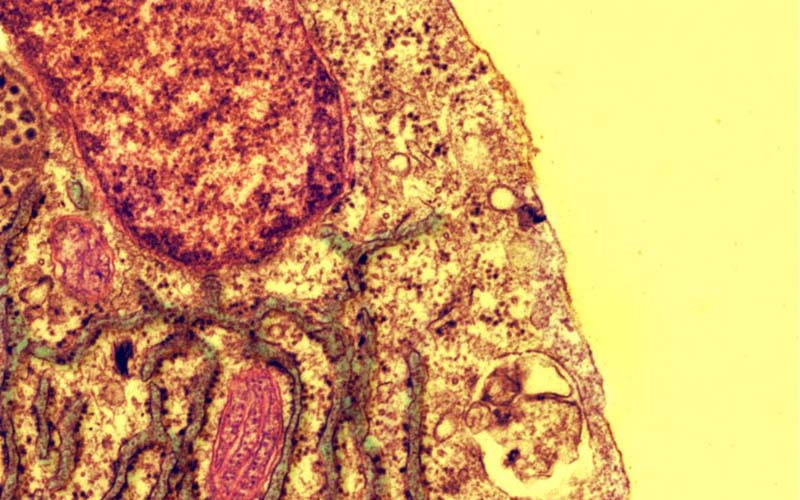

如今,先進的醫療設備不僅能幫助醫生診斷疾病,它們還可以為人們展現一種別樣的美麗。英國《每日郵報》7月27日刊登了一組醫學圖像的照片,這些照片都是榮獲英國心臟基金會反射研究科學圖像比賽冠軍們的作品,其美麗令人驚嘆。

醫學專家們利用如核磁共振掃描,還有顯微鏡這樣的醫療設備,從一個全新的視角捕捉到了心臟的復雜性以及其神秘性。比賽最終的贏家是來自英國愛丁堡大學的吉利恩·格雷(Gillian Gray)、梅甘·斯維姆(Megan Swim)和哈里斯·莫里森(Harris Morrison),他們的作品《破碎的心》獲得了今年的最佳圖像獎。該作品利用了光學投影層析(OPT)這種新的技術,向人們展示了一只成年老鼠心臟的3D結構,十分引人注目。

據悉,這種光學投影層析技術可以在病人心臟病發作后更好地幫助專家檢查其受創程度,并且進行修復評估。許多其它圖像也引發了關注,這些圖像包括一發育嬰兒的斑馬魚狀心臟、掃描電子顯微鏡下血管的應激反應、人體心臟內部隔室掃描以及血管平滑肌細胞中的心形狀細胞核等。